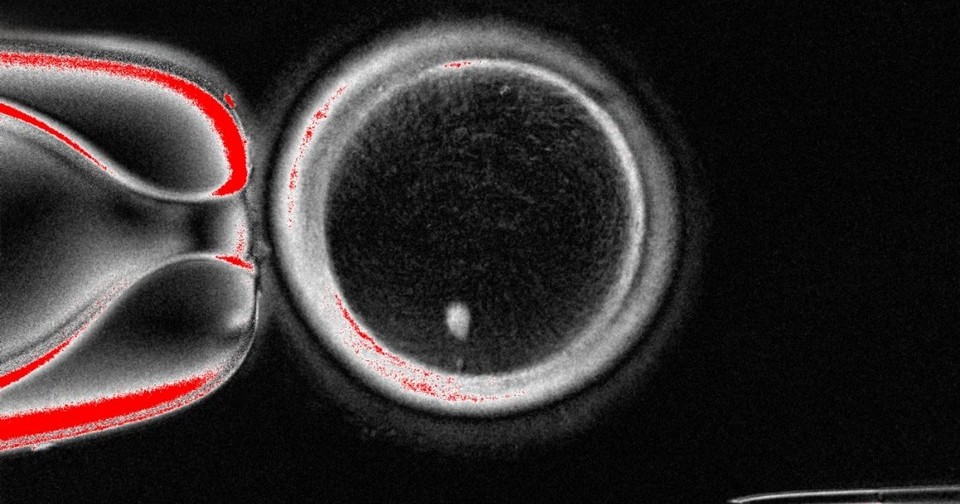

В новом исследовании Миталипов с коллегами перешел к экспериментам с человеческими клетками. У зрелых яйцеклеток, взятых у здоровых женщин, остановленных в фазе MII и содержащих полярное тельце первого деления, удалили комплексы веретен с хромосомами и перенесли в них остановленные на фазе G0/G1 ядра фибробластов человеческой кожи. После этого в них происходило преждевременное наступление метафазы без предварительной фазы S с формированием веретена деления de novo примерно через два часа после переноса. Эти клетки оплодотворили сперматозоидами методом ИКСИ, после чего 23,4 процента из них выделили полярное тельце и 17,4 процента сформировали пронуклеусы (против 82,9 и 79,8 процента у контрольных оплодотворенных яйцеклеток). Лишь 25 процентов от этого числа начали дробиться (против 100 процентов контрольных), однако процесс останавливался на стадии двух клеток, то есть окончательного выхода из фазы MII не последовало.

Чтобы решить эту проблему, исследователи разработали метод искусственной активации яйцеклеток, который состоит в их электропорации в D-сорбитовом буфере с ионами кальция (симулирующей повышение внутриклеточного уровня кальция после естественного оплодотворения) с последующим ингибированием митоз-стимулирующего фактора (MPF) росковитином. После этой процедуры 8,8 процента яйцеклеток с перенесенными ядрами развивались в бластоцисты.